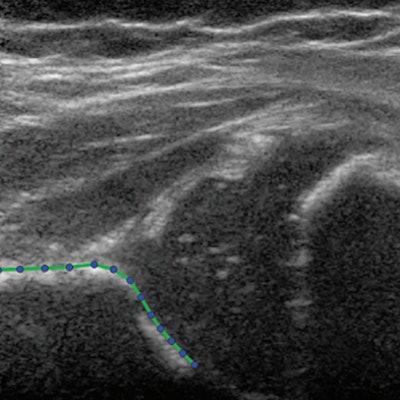

"Statistical shape modeling identified acetabular shape characteristics on ultrasound images of Graf type II hips that predict acetabular development and show a correlation with treatment," Bonsel and colleagues wrote. "The statistical shape modeling was also able to differentiate acetabular shape differences due to probe positioning from true anatomic variations."

Statistical shape modeling can quantify the shape of the acetabulum on ultrasound images. Bonsel et al said using ultrasound images can render more data for development of the hip than angle measurements alone.

The modeling created several shape modes from the 13 landmarks placed on ultrasound images of each hip. These modes showed shape variations of hip shapes on imaging sets.